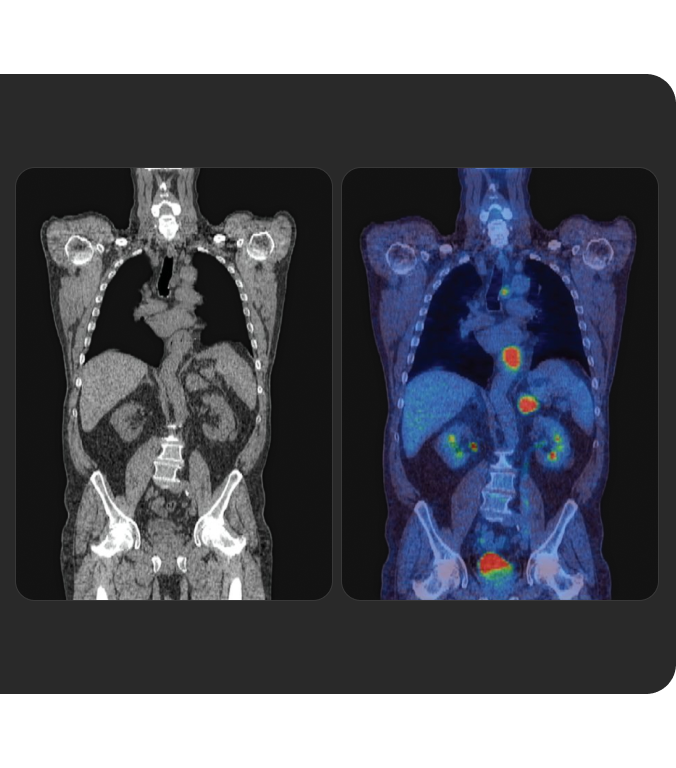

La Terapia con RadioLigandi (RLT) è un trattamento di precisione che rappresenta un'innovazione importante in ambito oncologico.

Scopri la RLT, le basi di questa forma di medicina di precisione e come Novartis sta gestendo la somministrazione continua della RLT ai pazienti in tutto il mondo.